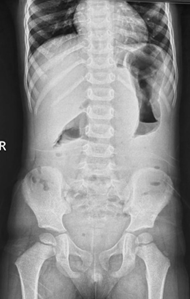

However, in small bowel obstruction, there is too much gas in the small bowel loops compared to the colon. Conversely, in colon obstruction with intact ileocecal valve, there is too much gas in the colon (Figure 3) compared to the small intestine and there is little or no gas in the rectum.5 The lack of gas in the rectum, however, is a late sign of bowel obstruction, so patients who present early in their disease process may have gas in the rectum on radiograph.

Figure 3 Anteroposterior supine abdominal radiograph in a 4-year-old child showing dilatation of bowel with smooth walls with too much gas in colon (haustra can be seen to identify colon) and absence of gas in the rectum suggestive of distal large bowel obstruction at level of rectosigmoid junction probably due to Hirschsprung’s disease.